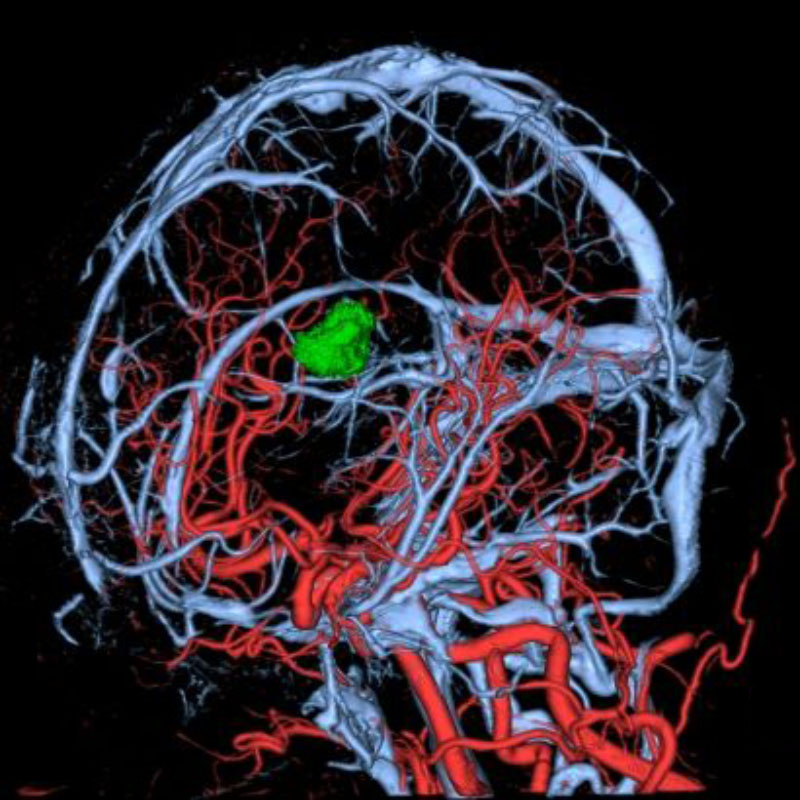

脳動静脈奇形

血管塞栓術

松田/濵田/元永